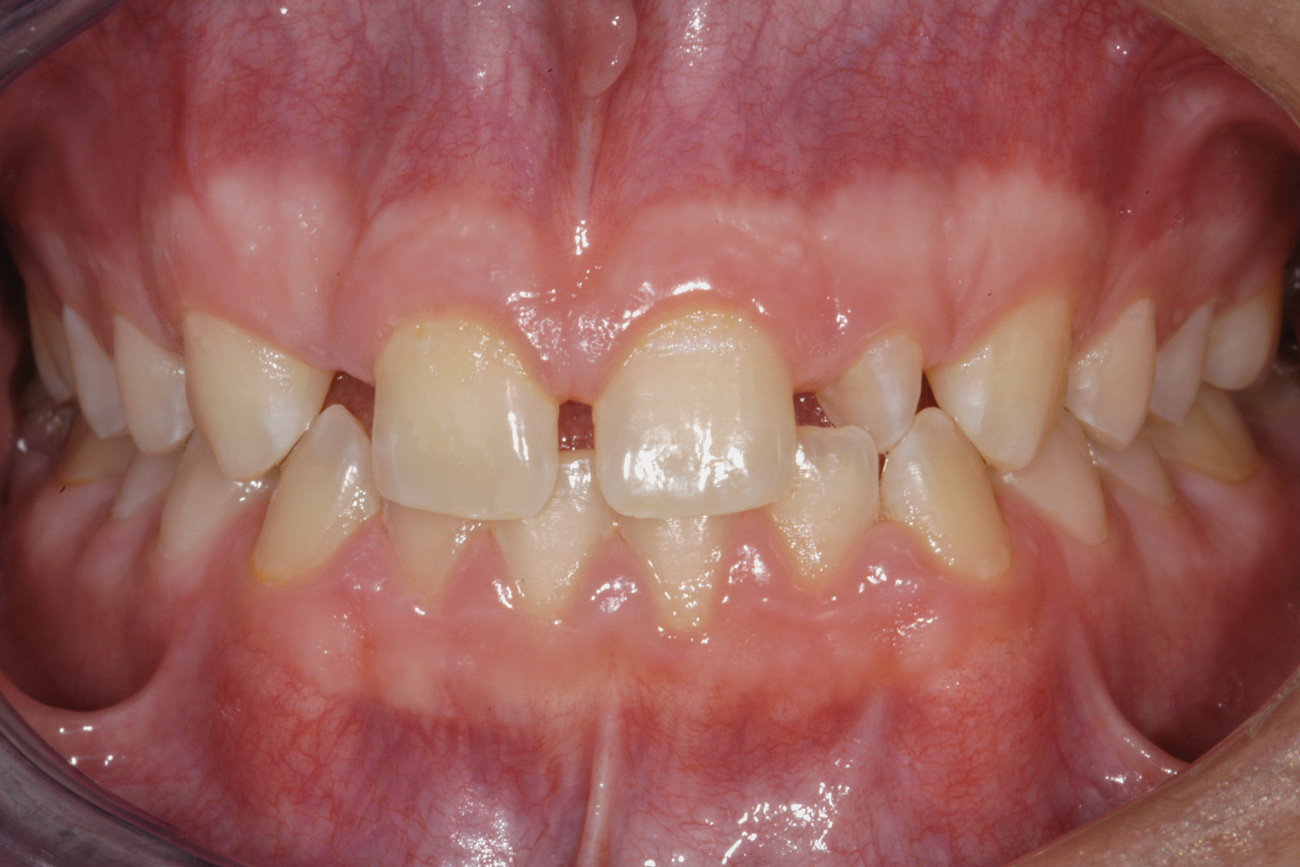

Fig 2. After orthodontic alignment of teeth and bleaching. Note alveolar deficiency in right lateral incisor site and diminutive left lateral incisor.

Figure 2

After 2 years of orthodontics, the appliances were removed, and his tooth coloration was improved using carbamide peroxide bleaching (Figure 2). Because some form of provisional needed to be placed until he was finished growing, a double-wing metal resin-bonded bridge was chosen. As discussed earlier, this is the ideal transitional prosthesis for patients that have congenitally missing maxillary lateral incisors. The benefits of this type of prosthesis include its ability to be removed and rebonded during the surgical phase of treatment and its ability to retain the roots in their proper position after orthodontic treatment.16 The final plan for the patient was to increase the width of the central and the maxillary left lateral incisor, utilizing porcelain laminate veneers to achieve the appropriate width/length ratio of 80%. A wax-up was created to idealize tooth size, a putty matrix was made from the wax-up to facilitate bonding of the incisors, and a non-precious, double-wing metal resin-bonded bridge was fabricated for lateral incisor replacement.